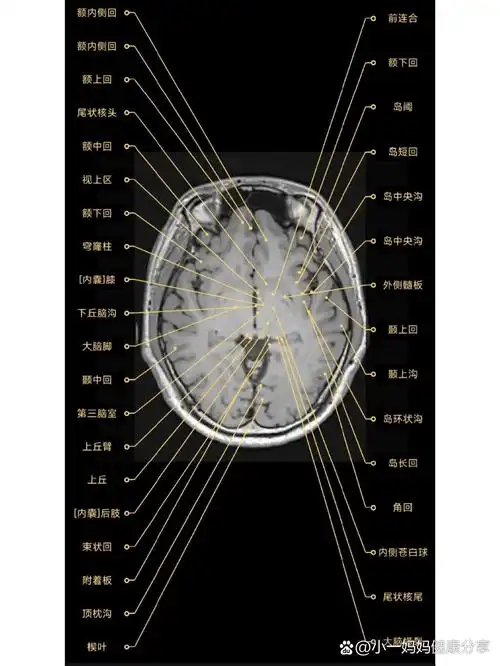

2. 第三脑室解剖图片

关键词 第三脑室解剖图片

第三脑室上部层面